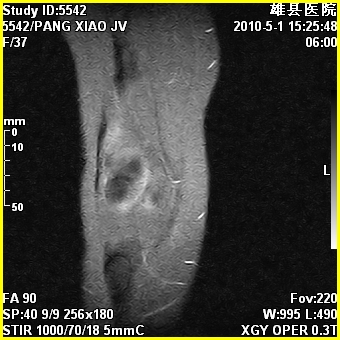

右股骨下端前内侧类圆形异常信号,位于干骺端,呈长t1长t2改变,但信号不均,t1图上病灶中心见小片状稍高信号影,t2图上见散在稍低信号影,stir像呈高信号,因病灶较小,缺乏特征性改变,结合患者年龄及部位,考虑嗜酸性肉芽肿可能性大。胫骨关节面下的小囊状异常信号,如果一元论考虑则为嗜酸性肉芽肿,不过发生在这个部位的少见,二元论考虑为邻关节骨囊肿。半月板与前后交叉韧带均未见异常。